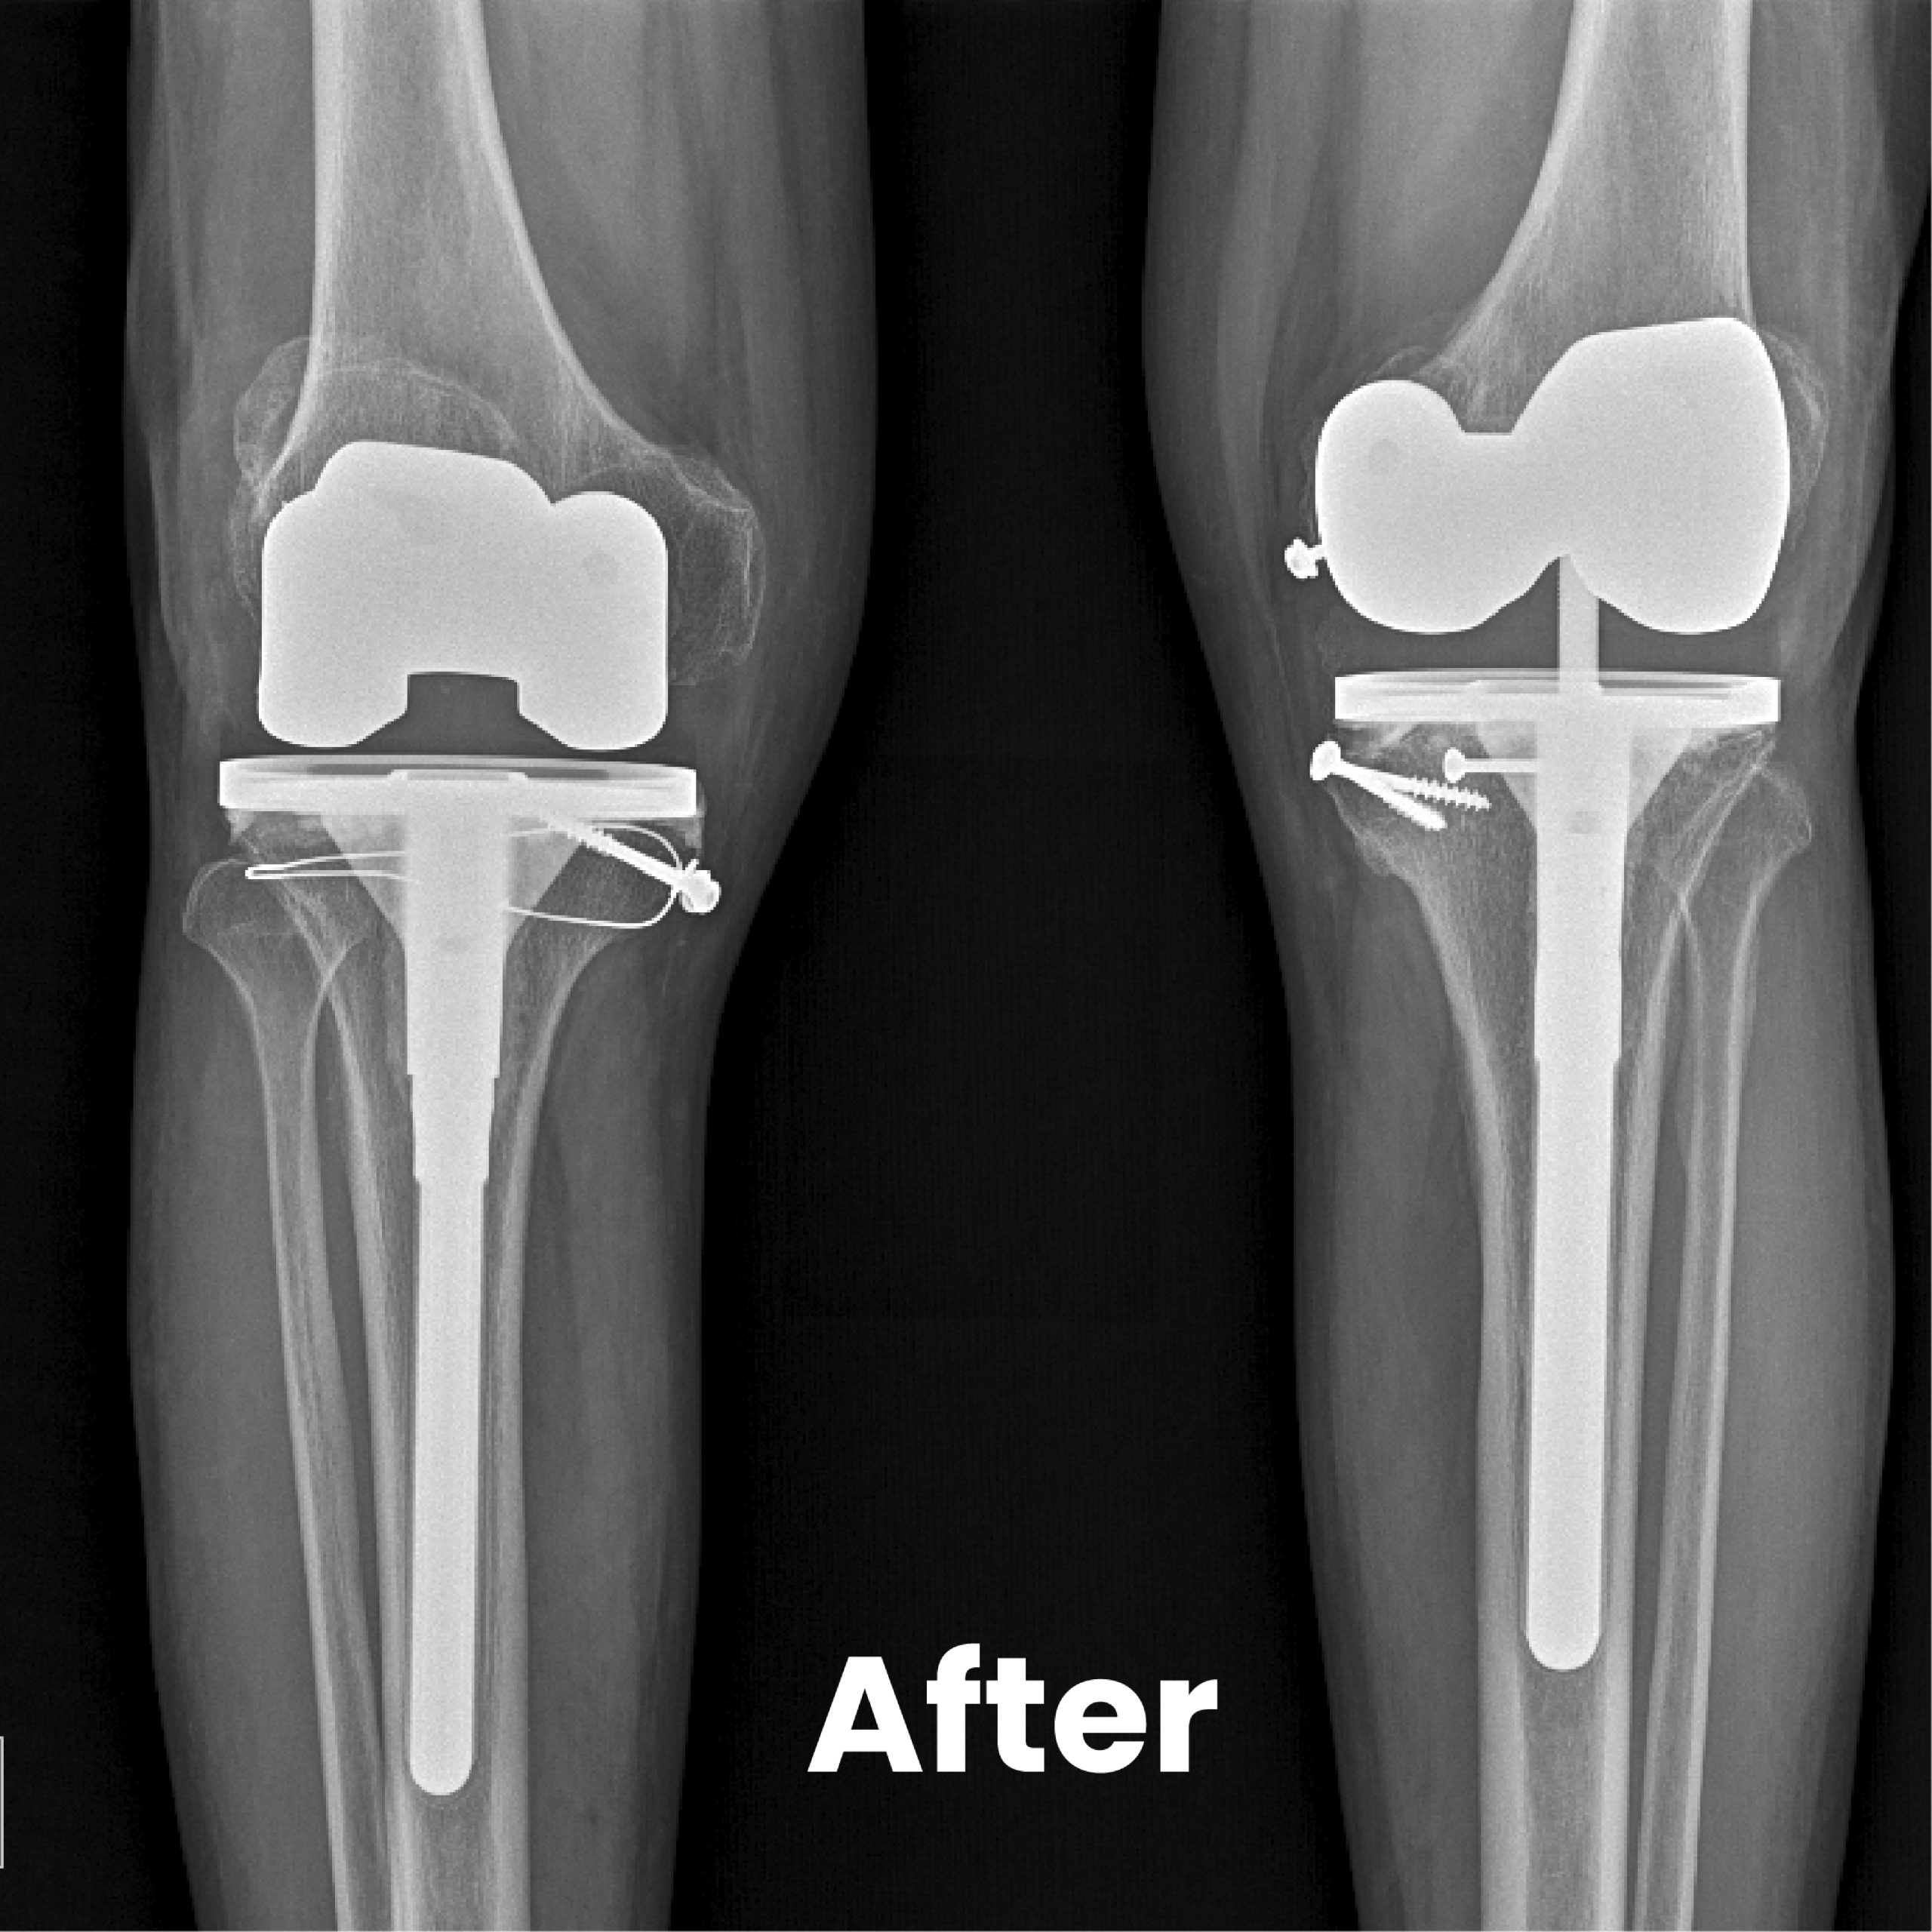

Senior surgeons with experience and expertise in the field perform knee replacement. Therefore, even complex deformed knee could be restored to normalcy. Pre-operative planning to post operative rehabilitation through surgical procedure is planned ahead so that nothing is left to chance. We are proud that our post operative infection rate is maintained at nil status for the past 5 years, thanks to the exceptional infection control measures. The type of implants is chosen after through discussion with the patient.